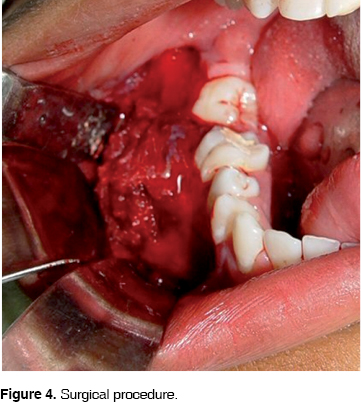

Under general anesthesia and nasotracheal intubation, an outlining incision was designed with distal retromolar extension and anterior vestibular, mucoperiosteal flap elevation, complete curettage of the lesion, extractions of the involved teeth and surgical drilling of the borders, protecting the displaced alveolar nerve (Figure 4). First an absorbable haemostatic sponge was placed in the gap then the mucoperiosteal flap was sutured.